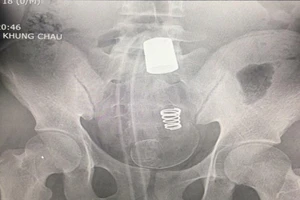

Lấy vòi xịt vệ sinh dài 45 cm từ hậu môn nam thanh niên